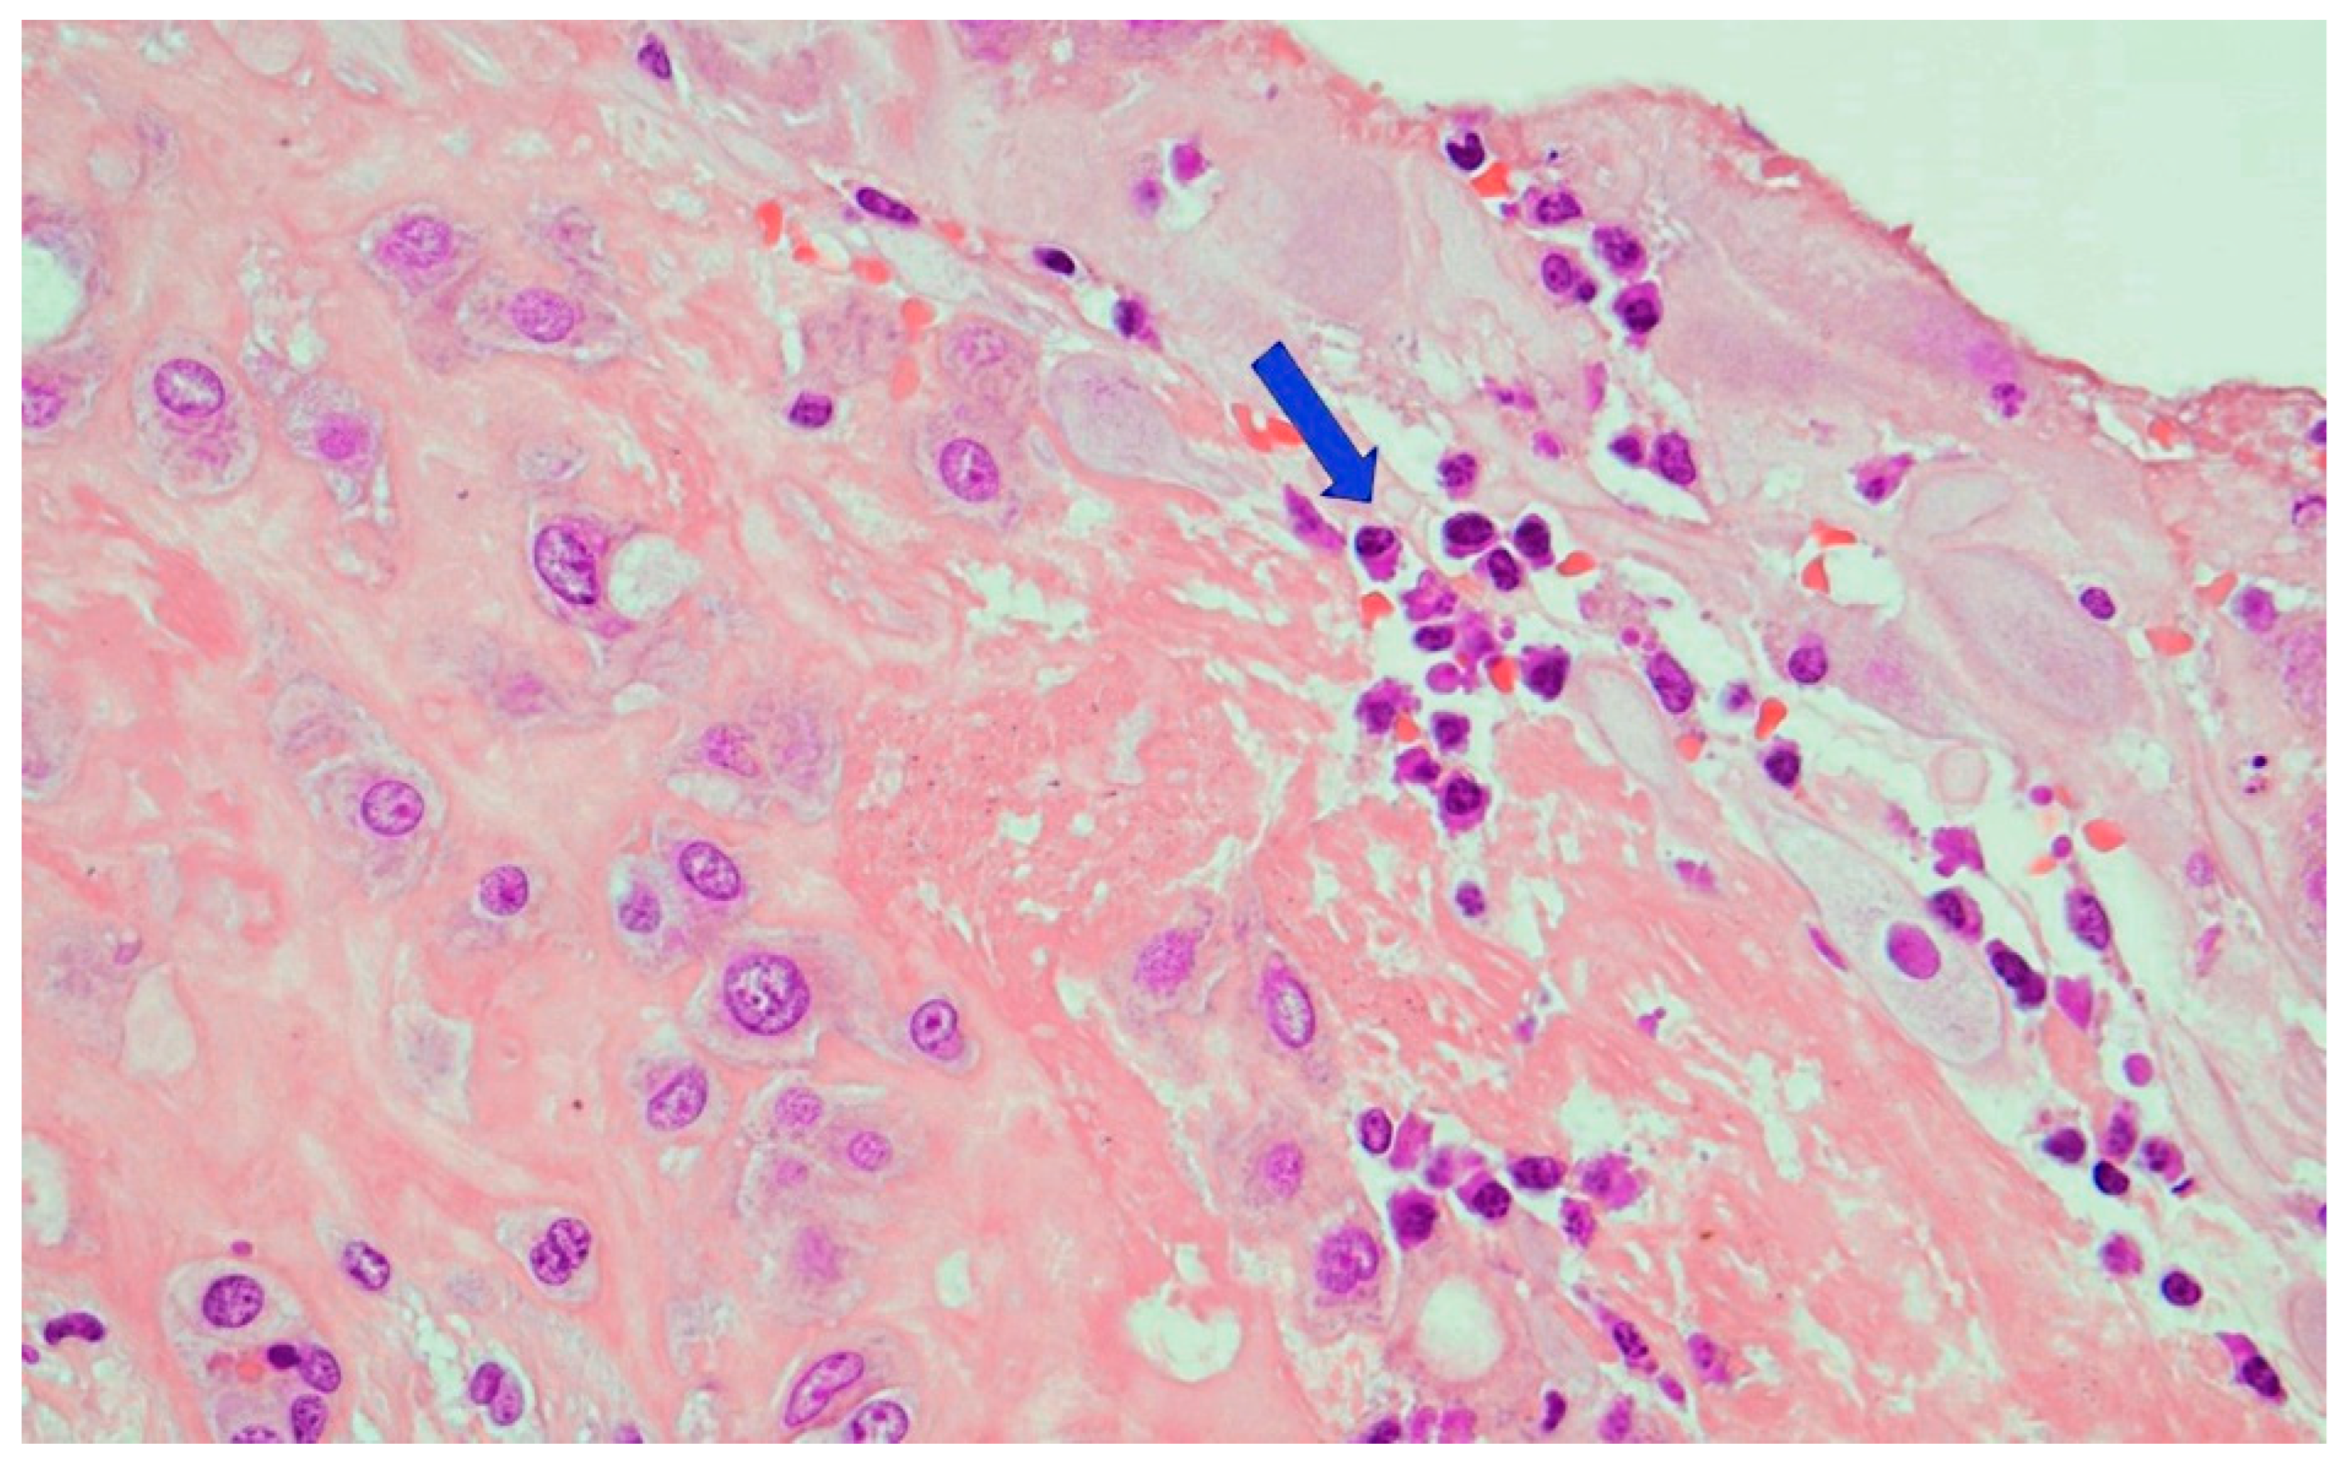

2. The Case